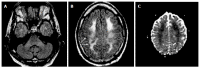

We describe common and less common diseases that can cause magnetic resonance signal abnormalities of middle cerebellar peduncles (MCP), offering a systematic approach correlating imaging findings with clinical clues and pathologic mechanisms. Myelin abnormalities, different types of edema or neurodegenerative processes, can cause areas of abnormal T2 signal, variable enhancement, and patterns of diffusivity of MCP. Pathologies such as demyelinating disorders or certain neurodegenerative entities (e.g., multiple system atrophy or fragile X-associated tremor-ataxia syndrome) appear to have predilection for MCP. Careful evaluation of concomitant imaging findings in the brain or brainstem; and focused correlation with key clinical findings such as immunosuppression for progressive multifocal leukoencephalopahty; hypertension, post-transplant status or high dose chemotherapy for posterior reversible encephalopathy; electrolyte disorders for myelinolysis or suspected toxic-drug related encephalopathy; would yield an appropriate and accurate differential diagnosis in the majority of cases.